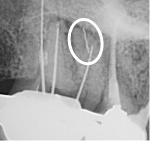

We developed the GentleWave® Technology in pursuit of improving the efficacy and efficiency of root canal treatment (RCT), as well as the patient experience. For well over a century, RCT has depended primarily on files to manually remove infected tissue and tooth structure from inside the tooth. Files, however, have limited reach inside complex root canal anatomy4 and can leave behind infected tissue3 and bacteria, leaving the tooth susceptible to reinfection.

The minimally invasive1 approach of the GentleWave Procedure minimizes manual instrumentation1,3 and instead utilizes a powerful vortex of procedure fluids3 and acoustic energy that cleans the deepest, most complex portions of the root canal system.1,3